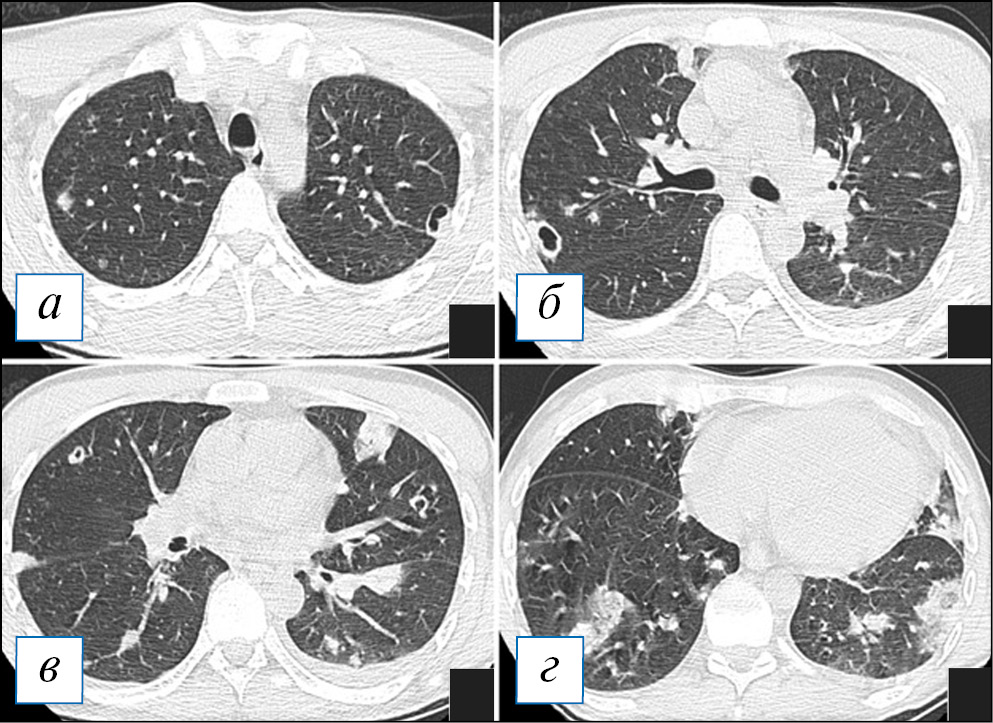

При проведении КТ органов грудной клетки отмечается уплотнение, чаще в виде консолидации или по смешанному типу, в сочетании с «матовым стеклом» пораженной части легкого, которая может быть несколько увеличена в размерах (рис. 2, Б), что объясняется скоплением экссудата и отеком легочной паренхимы по типу «выбухающей борозды». На фоне уплотнения быстро происходит деструкция легочной ткани в виде множественных очагов или более обширных участков; в начале этого процесса в полостях распада можно наблюдать некоторое количество содержимого с горизонтальным уровнем; секвестры нехарактерны (рис. 2). Внутренняя стенка полостей имеет четкий контур, что объясняется дренированием содержимого через бронхи, которые в ряде случаев прослеживаются (рис. 3). Может отмечаться выраженная реакция плевры, с развитием выпота или даже эмпиемы и пиопневмоторакса, особенно при формировании свища [8, 9, 40]. Негативными последствиями некротизирующей пневмонии может являться формирование фиброза с бронхоэктазами, персистирование полостей распада при отсутствии их спадения, а также облитерация плевральной полости на уровне воспалительного процесса [39].

Рис. 2. Компьютерная томография органов грудной клетки в аксиальной проекции (а–г). Двусторонняя полисегментарная пневмония. С обеих сторон в легких, больше справа, имеются инфильтраты, на фоне которых просматриваются полости различного размера без жидкостного содержимого. Незначительный пневмомедиастинум. [Изображения из архива авторов]. / Fig. 2. Chest CT, axial projection (а–г). Bilateral polysegmental pneumonia. On both sides in the lungs, more to the right, there are infiltrates and cavities of various sizes without liquid content. Minor pneumomediastinum. [Images from the authors’ archive].